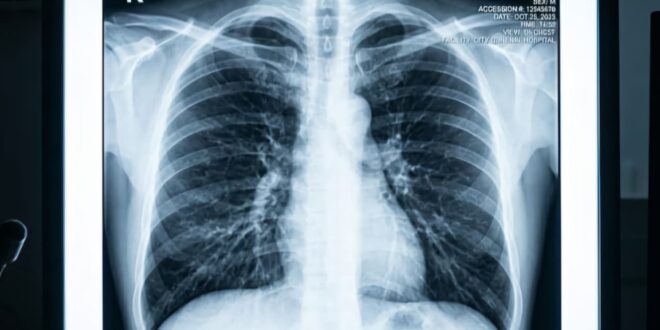

وقد بدأت هذه القصة في ربيع عام 2023، عندما أصيب الرجل البالغ من العمر 33 عامًا بفشل رئوي مرتبط بالإنفلونزا. وسرعان ما تطورت حالته إلى التهاب رئوي، وتسمم الدم، وما يُعرف بمتلازمة الضائقة التنفسية الحادة (ARDS).

ويقول جراح الصدر البروفيسور أنكيت بهارات: “أصيب [المريض] بعدوى في رئتيه لم تستجب لأي مضادات حيوية لأنها كانت مقاومة لجميعها”. ويتابع: “تسببت هذه العدوى في تسييل رئتيه[1]، ثم انتشرت إلى باقي أنحاء جسده”.

والنهج المعتاد هو وضع المريض على جهاز دعم الحياة ومنح الرئتين الوقت الكافي للتعافي. لكن في هذه الحالة، كانت الرئتان هما المشكلة الرئيسية ومصدر العدوى: بدا أن الرجل سيموت حتمًا إن لم تُستأصل رئتاه، ومرجحًا جدًا أن يموت إن استُؤصلتا.

وقد أجرى البروفيسور بهارات وفريقه تحليلًا جزيئيًا للرئتين بعد استئصالهما، مؤكدين عدم وجود أي فرصة لتعافي الرئتين من متلازمة الضائقة التنفسية الحادة من تلقاء نفسيهما. وبسبب التندب وتلف الجهاز المناعي، كانت زراعة الرئة ضرورية للغاية في هذه الحالة.